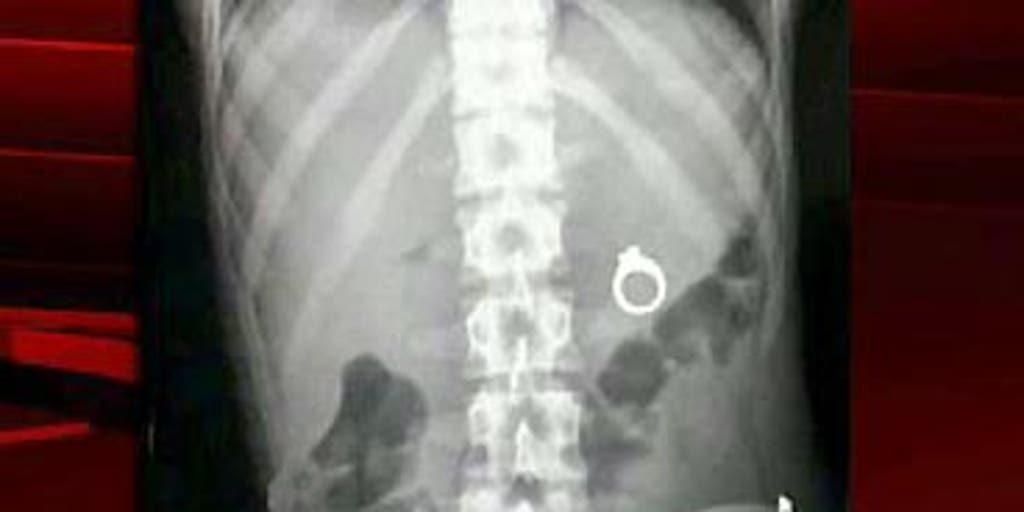

ок проглотил кольцо

Ребенок проглотил кольцо 116 фото